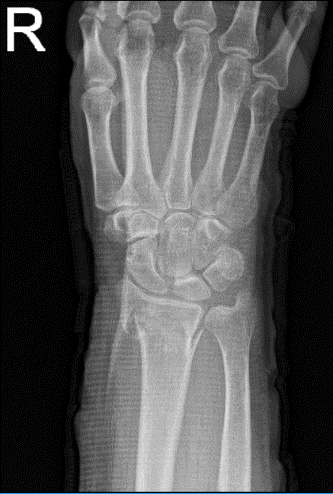

A 69 year-old patient was in our office with complaints regarding pain and deformity in right wrist. She got a sugar tong splint there and is now in NY. She got the pain due to falling. For aggravating factors, the patient reports pushing/pulling and weight bearing.

For associated symptoms, she reported weakness, swelling, tender to the touch, and pain with motion but reported no numbness, no tingling, no redness, no warmth, no ecchymosis, no catching/locking, no popping/clicking, no buckling, no grinding, no instability, no radiation, no drainage, no fever, no chills, no weight loss, and no change in bowel/bladder habits.

The patient presented an MRI result which contained Colles’ fracture with dorsal angulation.

Right wrist X-ray 3 or more views